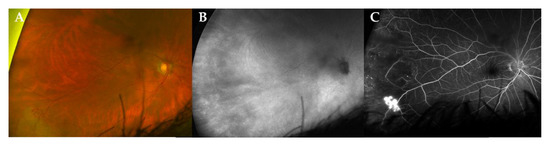

During follow-up, two patients developed a neovascularization (NV) (case 3, left eye retinal NV after 86 months (Figure 2); case 4, type 2 macular NV right eye after 36 months, (Figure 3)) [12].

Figure 2. Multimodal imaging of a peripheral retinal neovascularization in a patient with stable disease. Ultra-widefield (UWF) fundus photography (CF, panel (A)), indocyanine green angiography fundus imaging (ICG, panel (B)) and fluoresceine angiography (FA, panel (C)) of a 72-year-old male patient (case 3) at 86 months of follow-up. Note the active retinal neovascularization in the temporal periphery. In this case, the use of ICG could not demonstrate a choroidal lesion.